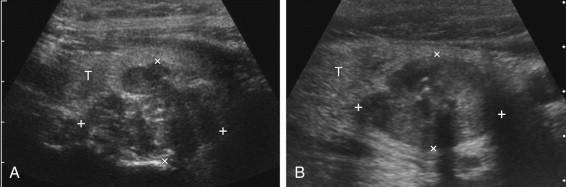

In approximately 80% of patients, thyroid hyperplasia is idiopathic, related to iodine deficiency, familial causes, or medications. An enlarged, hyperplastic gland is called a goiter . The male-to-female ratio is approximately 1 : 3. When hyperplasia progresses to nodule formation, the pathologic designation of the nodules may be hyperplastic, adenomatous, or colloid. Nodular hyperplasia is the most common cause for thyroid nodules. These types of nodules share some common sonographic appearances ( Fig. 10-5 ). They very frequently have cystic components. When the nodule is small, the cystic components are also very small. As the nodule enlarges, the cystic spaces may also enlarge. When cystic elements are predominant, they are usually associated with multiple internal septations, thick walls, solid or partially solid mural nodules, or a combination of these features. Diffusely scattered cystic spaces of variable size with little solid tissue can produce a spongy appearance that is another typical feature of nodular hyperplasia. The echogenicity of the solid components of nodular hyperplasia is variable and may be hypoechoic, isoechoic, or hyperechoic compared with normal parenchyma. Nodular hyperplasia varies in vascularity, but usually has detectable internal flow and is often hypervascular.

F igure 10-5, Nodular hyperplasia (cursors) in different patients. A, Spongy lesion. B, Cystic lesion with multiple internal septations and minimal solid components. C, Cystic nodule with solid mural nodule (arrows) that contains multiple comet-tail artifacts. D, Cystic nodule with a thick wall. E, Solid nodule with multiple scattered cystic components. F, Dual gray-scale and color Doppler views show a hypervascular, predominantly solid nodule with small, scattered cystic components.

Crystals that precipitate in colloid are often present in nodular hyperplasia and can produce scattered, tiny, bright, nonshadowing reflections. In some cases there is an associated comet-tail artifact that distinguishes them from microcalcifications (see Fig. 10-5C ). In other cases they are not appreciably different from microcalcifications. Comet-tail artifacts that are recognizable on real-time scanning may be difficult to perceive on static images ( e-Fig. 10-3 , ). In general, tiny, nonshadowing, bright reflections within cystic spaces are more likely to be crystals associated with nodular hyperplasia. Nodular hyperplasia can occasionally simulate follicular neoplasms and papillary cancer ( Fig. 10-6 ).

F igure 10-6, Atypical nodular hyperplasia. A, Isoechoic nodule (cursors) that is predominantly solid but contains a few large cystic spaces simulates a follicular neoplasm. B, Solid, isoechoic nodule with a peripheral hypoechoic halo simulates a follicular neoplasm. C, Solid, hypoechoic nodule with microcalcifications simulates papillary cancer.